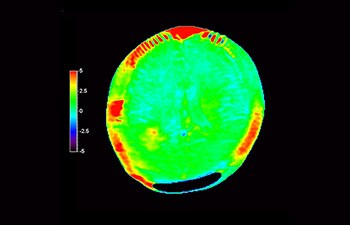

In a society where neurological disorders represent a heavy burden, Philips is committed to provide superb diagnostic clarity and treatment guidance for all patients. Today, although MR is the gold standard in neuro oncology imaging, its accuracy in tumor grading and treatment follow up assessment can be further improved. 3D APT (Amide Proton Transfer) is a unique, contrast-free, brain MR imaging method addressing the need for more confident diagnosis in neuro oncology. 3D APT uses the presence of endogenous cellular proteins, to produce an MR signal that directly correlates with cell proliferation, a marker of tumoral activity. 3D APT can support trained medical professionals in differentiating low grade from high grade gliomas and, in differentiating tumor progression from treatment effect1.